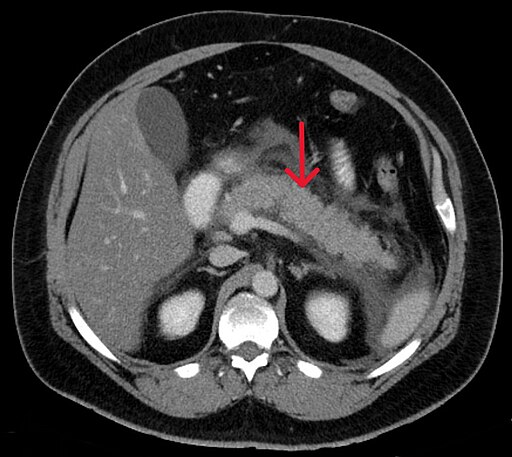

Akute Pankreatitis

DefinitionAkute Pankreatitis

ist eine plötzlich auftretende Entzündung der Bauchspeicheldrüse, die sich meist durch starke, gürtelförmige Oberbauchschmerzen äußert, die in den Rücken ausstrahlen.

Pankreatitis exsudativ CT axial.jpg von Hellerhoff, CC BY-SA 3.0, via Wikimedia Commons